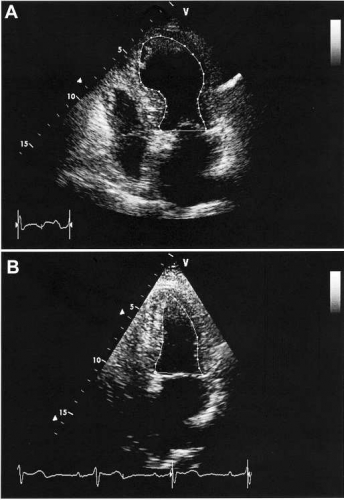

Initiala respektive maximala troponin I-värden uppmättes till 0,79 respektive 3,21 (my)g/l. Koronarangiografi utfördes akut och visade friska kranskärl utan ateromatos. Ekokardiografi samma dag visade akinesi och vidgning av vänster kammares apikala halva, medan de basala segmenten var hyperkontraktila (Figur 5 A). Ejektionsfraktionen skattades till 35–40 procent. Patienten skrevs ut i gott skick efter sex dagars vårdtid.

Vid kontroll fyra veckor efter hemgång var vänsterkammarfunktionen helt återställd utan påvisbara hypokinesier och med en ejektionsfraktion på >55 procent (Figur 5 B). På EKG noterades uttalade T-inverteringar i flertalet avledningar, vilka dock efter ny kontroll åtta månader senare gått i regress (Figur 4). Under de två år som passerat efter insjuknandet har patienten varit besvärsfri.

Ekokardiografiskt ser man typiskt dilatation och utbredd kontraktionsnedsättning i vänster kammares apikala halva (Figur 5 A). Väggrörligheten i den basala kammarhalvan är oftast normal eller hyperkontraktil. Ejektionsfraktionen är vanligen reducerad i det akuta skedet. Hyperkontraktilitet i de basala delarna av vänster kammare kan i vissa fall ge upphov till en subvalvulär obstruktion i vänster kammares utflödesområde [11]. Denna utflödesobstruktion kan förvärras av inotrop behandling och leda till hypotension.